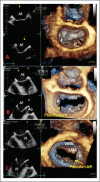

Three-dimensional Echocardiography Reveals the True Enemy in a Young Male with ST-Elevation Myocardial Infarction and Severe Mitral Regurgitation: Posterior Mitral Valve "Pseudo-Cleft" and Prolapse